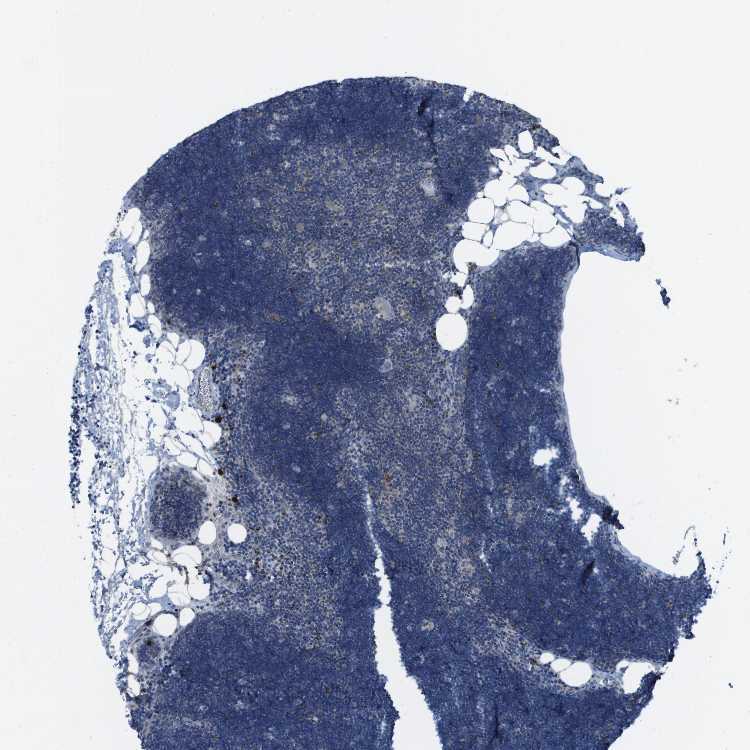

TISSUE PRIMARY DATA LYMPH NODE Show tissue menu

Lymph node

LYMPH NODE - Expression summary

LYMPH NODE - Antibody stainingi

Antibody staining in the annotated cell types in the current human tissue is reported as not detected, low, medium, or high, based on conventional immunohistochemistry profiling in selected tissues. This score is based on the combination of the staining intensity and fraction of stained cells.

Each image is clickable and will lead to virtual microscopy that enables deeper exploration of all samples and also displays staining intensity scores, fraction scores and subcellular localization as well as patient and tissue information for each sample.

Antibody HPA012716

Germinal center cells High

Non-germinal center cells High